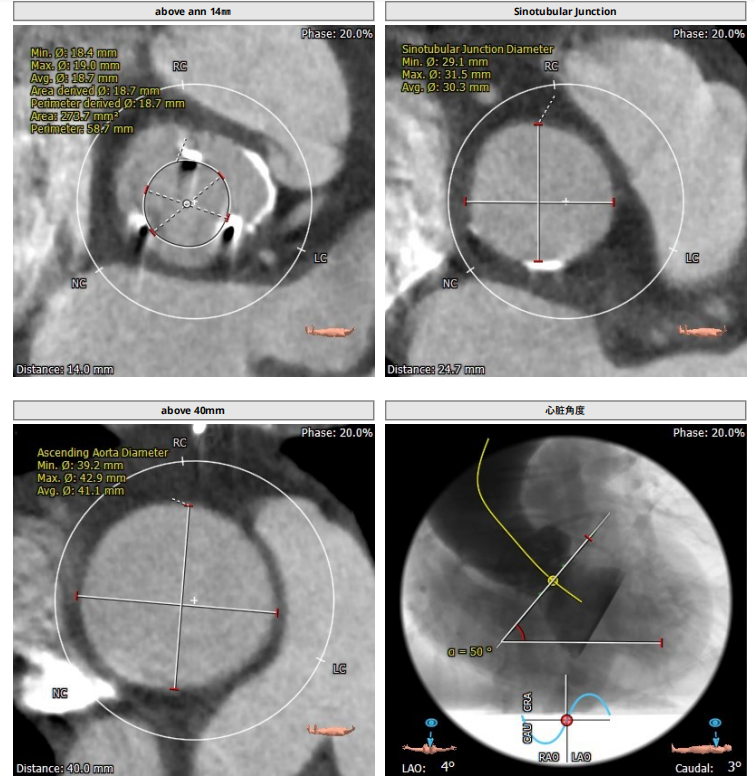

术前CT评估报告

1、入路条件差,髂动脉血管钙化十分严重,通路建立难度极大。

2、主动脉瓣置换术后,瓣口面积极小,导致瓣膜无法稳定锚定,需要术中时刻观察调整。

3、升主动脉最宽处约44.5mm,心脏角度大,约50°,备Snare辅助。